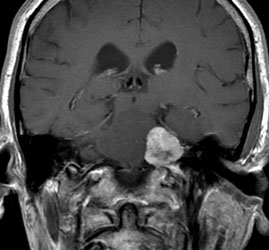

Imagerie IRM :

Large lésion développée dans l’angle ponto-cérébelleux gauche. Très discrète extension visible au niveau du porus intracanalaire. Persistance de la visibilité du LCS au fond du MAI. Lésion hétérogène en iso- et hypersignal T2. Très important rehaussement périphérique à centre hypointense « nécrotique » en T1 après injection de gadolinium.